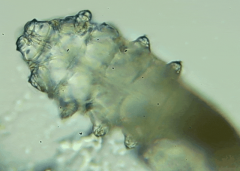

人体上寄生着两种蠕形螨,分别是毛囊蠕形螨和皮脂蠕形螨,他们通常呈乳白色、半透明的细长状,拥有四对脚,以睫毛囊上皮细胞、腺体内脂质为食物,因此主要寄生在面部、眼睛、头皮等地方,其中寄生在眼睛里的蠕形螨主要活动在睫毛毛囊、睫毛皮脂腺,以及睑板腺里。

蠕形螨完全长大也只有0.1-0.2毫米,因此肉眼难以看到它们,只有在电子显微镜下我们才能看到睫毛根部的一只只蠕形螨。这些螨虫每天都很活跃,且繁殖速度极快,完成一代生活史仅需大概15天。

在检查的时候,医生要在每个眼睑上拔出几根比较典型的睫毛,然后放在光学显微镜下,寻找有没有螨虫。